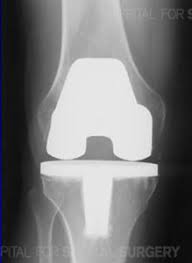

If the Lord tarries, my total knee replacement surgery will be on Monday, November 8. I visited three rehabilitation (rehab) facilities and chose the nicest one with a private room and private bath. I will pay $20 extra per day for a private room, but it is worth it since I am such a light sleeper. I don’t want to end up with a roommate who screams all night. This facility specializes in joint rehab and has an excellent reputation. My sister, Marsha, is flying here on November 6 and will be with me through the 15th. My dad offered to give me money every month while I am out of work. How I thank God for their help.

I went to an interesting class at the hospital to prepare me for surgery. They gave me a folder and had me watch a video by a TV actor who had both his knees replaced at the same time. He is now able to ride a horse, so maybe I can cross-country ski next winter. Dr. S. told me not to give away my skis.

I had my surgery one week ago, and I’m now at the rehab facility in my pleasant private room. Marsha flew back to her home today. She was my advocate while I was in the hospital when I could not think straight from the pain and anesthesia. I am so thankful for her help and the nurses from church. I thought I would lose my mind from the pain right after surgery. I fainted several times in the hospital from low blood pressure caused by the pain medicine, so the doctor gave me a different one. They put my leg in the continuous passive motion (CPM) machine which made me spasm, so I refused it.

And so I began my 10 day stay in the rehab unit. The intensity of the pain after surgery surprised me. The experts say bone pain is the worst kind of pain, especially in the knee joint because the swelling has nowhere to escape. People who have had both their hip and knee replaced told me the knee replacement pain was significantly worse. However, everyone experiences surgical pain differently. A few people only need mild medicine, but I experienced the opposite end of the spectrum. Probably because of my young age of 49 and intact nerves.